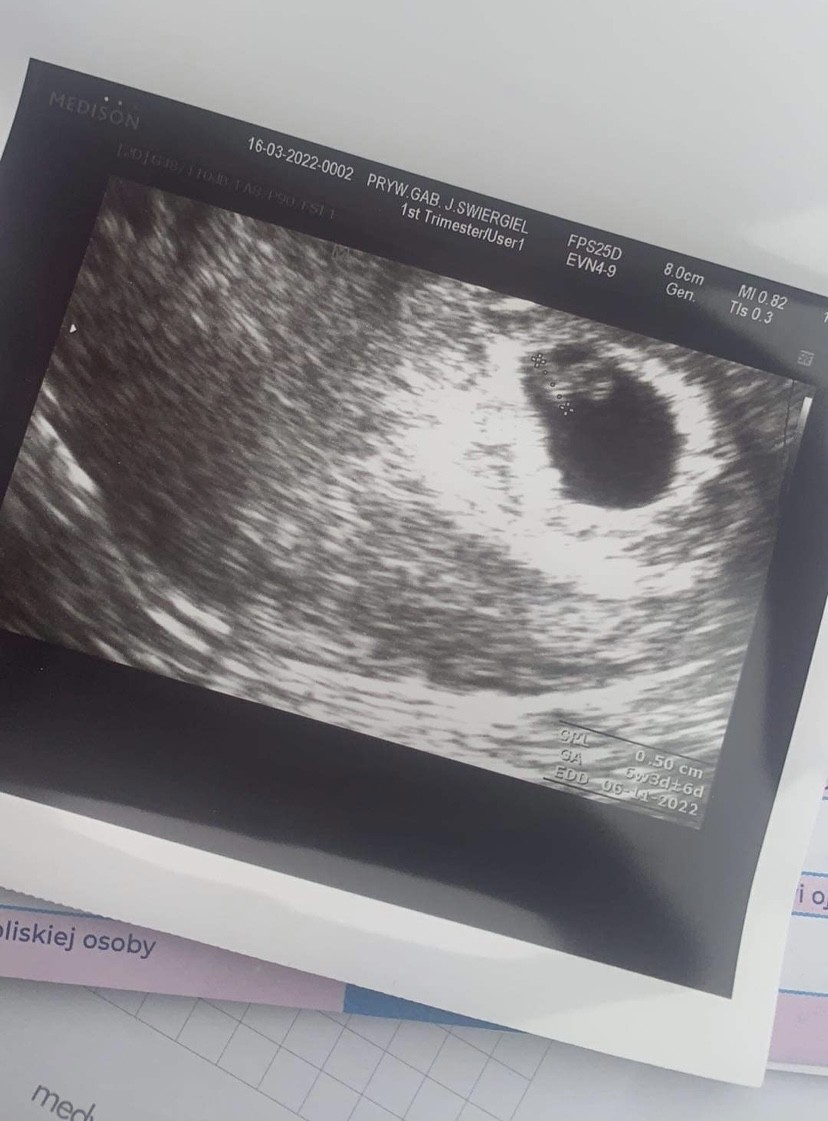

Jestem po wizycie. Jest zarodek i serduszko, wszystko w jak najlepszym porządku

Według USG jest to 6 tydzień i 3 dzień, czyli tak jak wynika z mojej ostatniej miesiączki

Nie mam żadnych krwiaków ani nic takiego, do końca nie wiadomo dlaczego są plamienia, ale mam się tym nie przejmować

Podobno czasami tak bywa. Profilaktycznie mam brać duphaston

Tak się cieszę! Kamień spadł mi z serca po tej wizycie